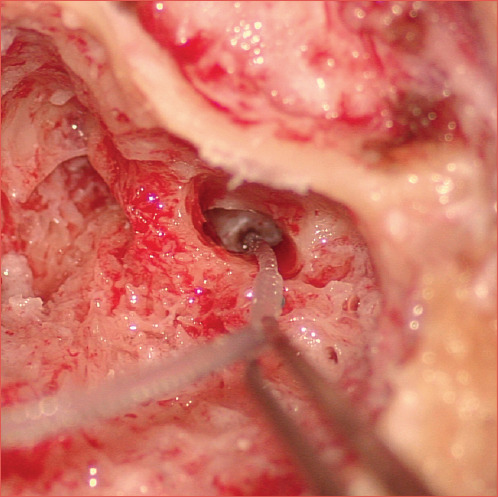

Abstract Image